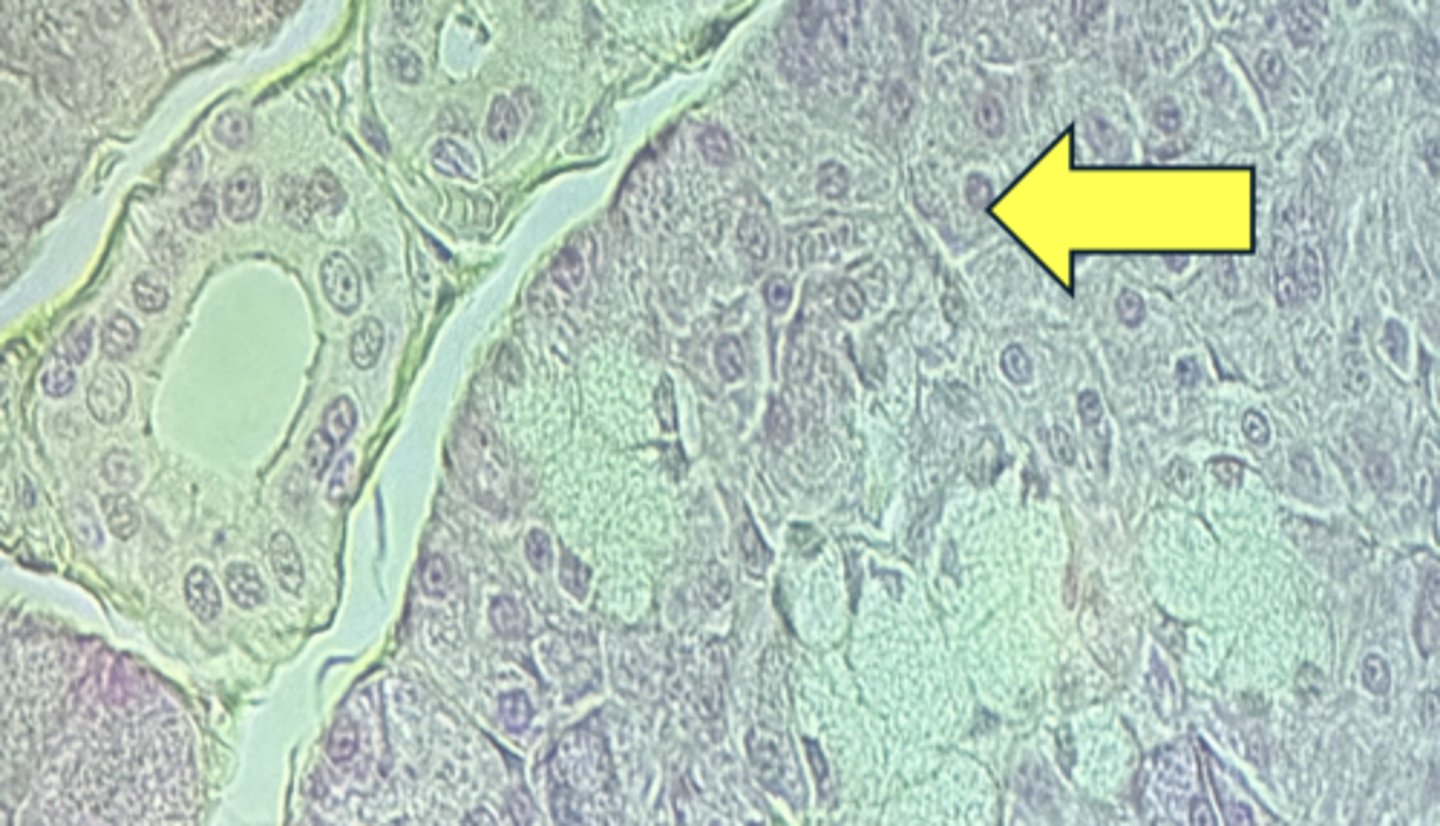

Pancreas

name the tissue

pancreatic islets

Acinar cells- digestive enzymes, amylase, lipase, & proteases

(pancreas)

type of cell & what it secretes?